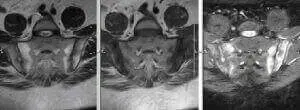

Найбільш показовою ознакою, наприклад, при хворобі Бехтерєва, є не тільки клінічний огляд, але і МРТ клубово-крижових зчленувань з використанням спеціальних режимів.